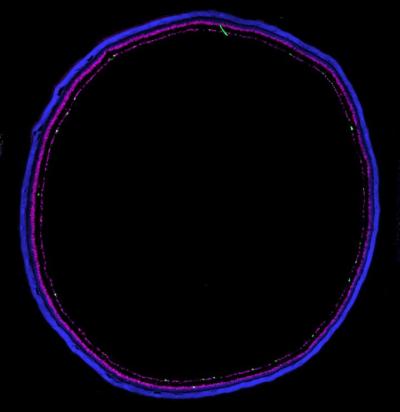

Purple, pink, white rings showing fluorescence from retina section

Retinal section from a mouse where cell nuclei are labeled in blue, inhibitory cells are labeled with magenta, and ipRGCs are labeled in green. Credit: Northwestern University